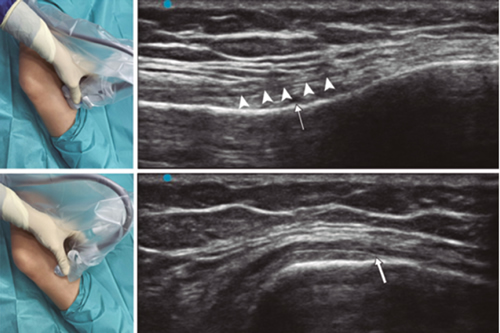

Figure 1